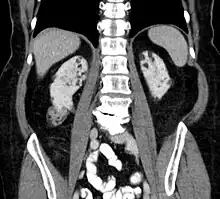

Kidneys

Between 26% and 80% of TSC patients have benign tumors of the kidneys called angiomyolipomas, with hematuria being the most frequent presenting symptom. [8] TSC angiomyolipomas differ from non-TSC angiomyolipomas in age of presentation (31.5 years vs 53.6 years), mean tumor size (8.2 cm vs 4.5 cm), and percentage of cases requiring surgical intervention (50% vs 28%).[8] Although benign, an angiomyolipoma larger than 4 cm is at risk for a potentially catastrophic hemorrhage, either spontaneously or with minimal trauma.